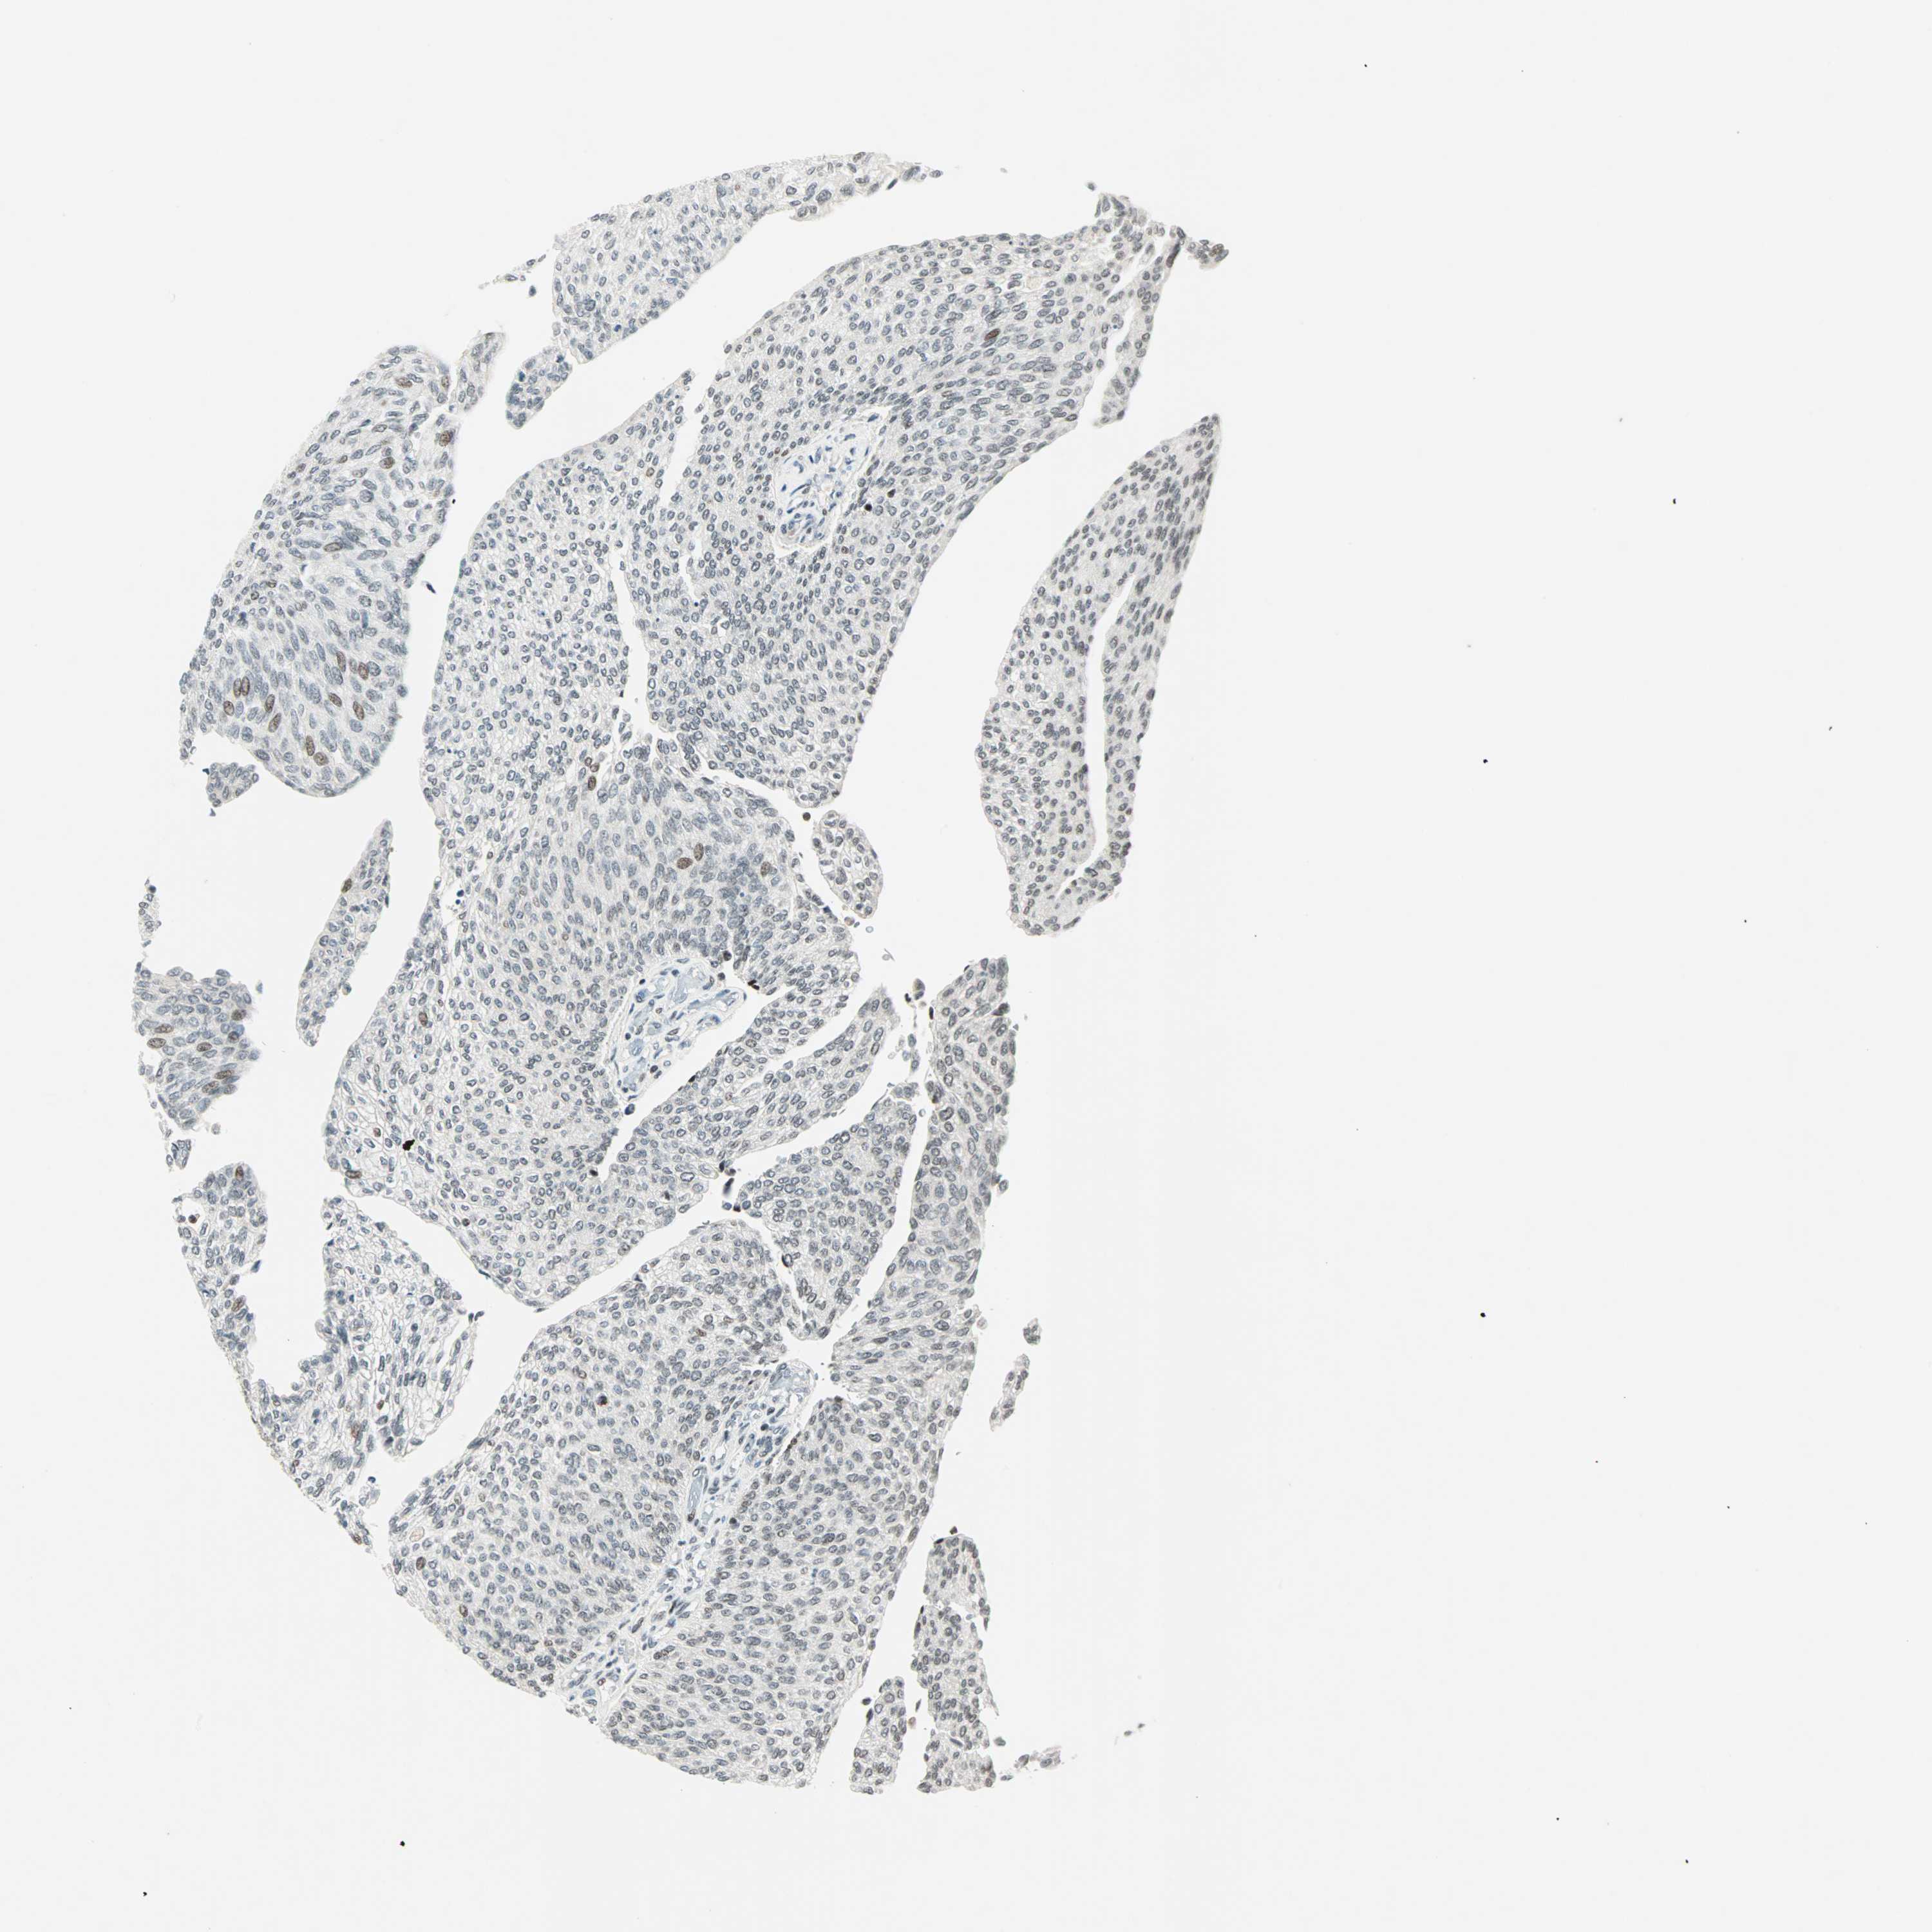

UROTHELIAL CANCER - Protein expressioni

A mouse-over function shows sample information and annotation data. Click on an image to view it in a full screen mode. Samples can be filtered based on level of antibody staining by selecting one or several of the following categories: high, medium, low and not detected. The assay and annotation is described here.

Note that samples used for immunohistochemistry by the Human Protein Atlas do not correspond to samples in the TCGA dataset.

Antibody stainingi

Antibody staining in the annotated cell types in the current human tissue is reported as not detected, low, medium, or high, based on conventional immunohistochemistry profiling in selected tissues. This score is based on the combination of the staining intensity and fraction of stained cells.

Each image is clickable and will lead to virtual microscopy that enables deeper exploration of all samples and also displays staining intensity scores, fraction scores and subcellular localization as well as patient and tissue information for each sample.

Antibody HPA047213

Antibody HPA062123

Antibody CAB004506

Urothelial carcinoma, High grade

Urothelial carcinoma, Low grade

Urothelial carcinoma, NOS